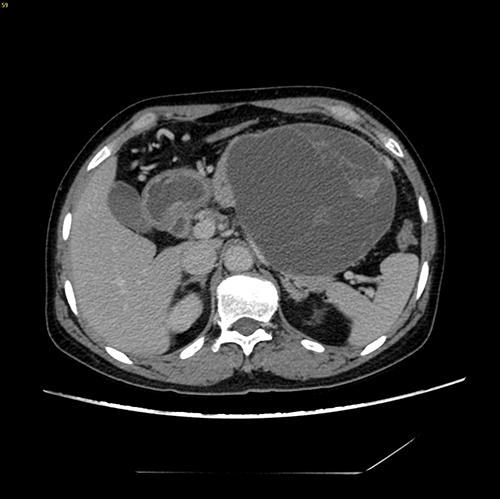

胰体尾囊腺瘤---腹腔镜胰体尾切除